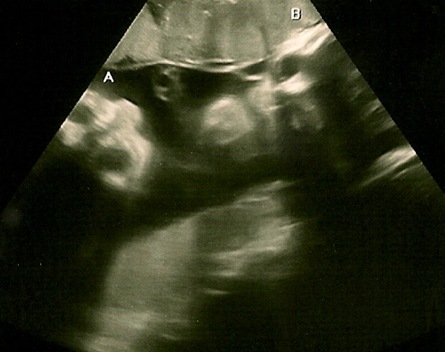

a rather creepy picture, but you can see both A and B’s faces.

B’s face – eye is closed and you can see his nose.